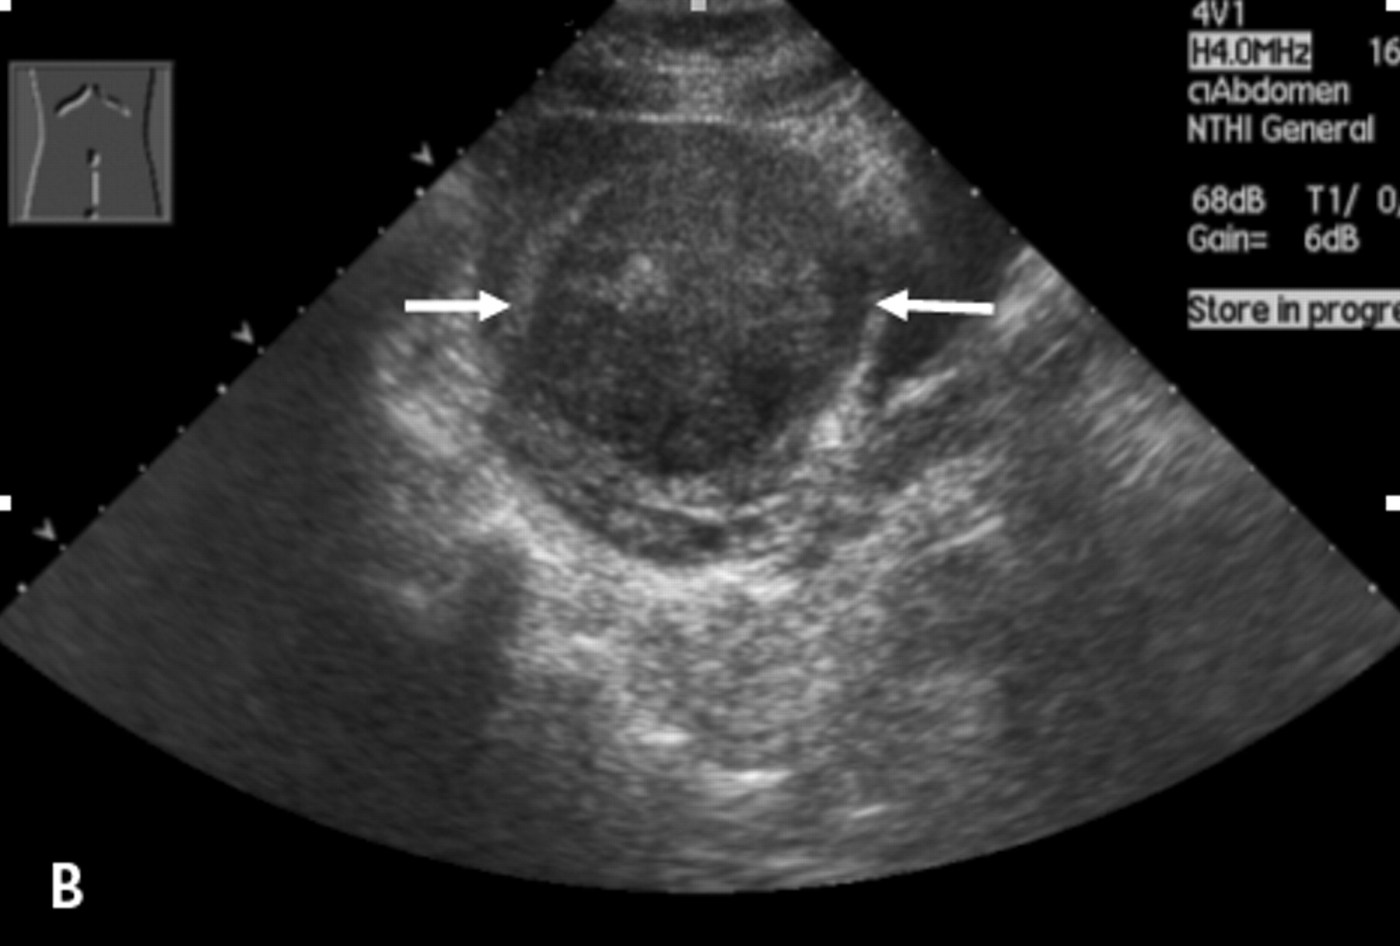

Freddy gets a big mention in my referral to the urologist. It describes my uterus as “bulky with an eggshell calcification measuring up to 7.6cm most likely degenerated fibroid”.